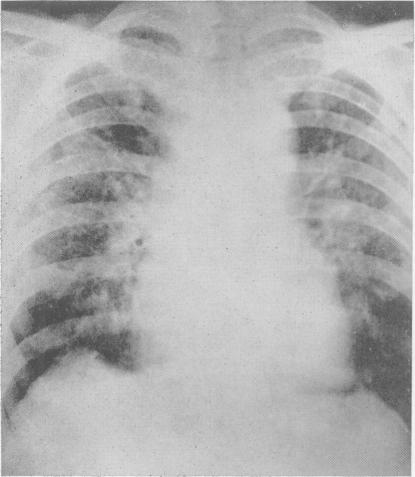

Radiology in the investigation and management of hypertension.

Postgrad Med J. 1958 Oct;34(396):514-23 passim. doi: 10.1136/pgmj.34.396.514.